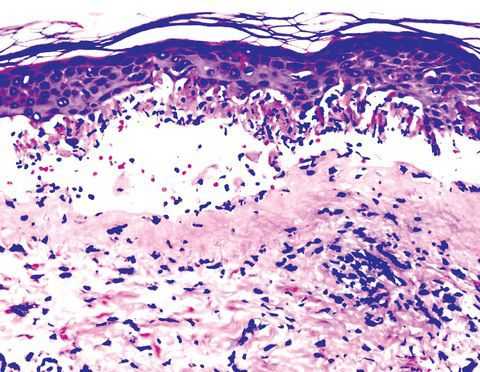

В затруднительных случаях для подтверждения диагноза узловатой эритемы дерматолог назначает биопсию одного из узловых образований. Гистологическое изучение полученного материала выявляет наличие воспалительного процесса в стенках мелких артерий и вен, в междольковых перегородках на границе дермы и подкожной клетчатки.

- Биопсия узла (редко). Гистологический анализ показывает наличие или отсутствие характерных клеток для узловатой эритемы в материале [7] .